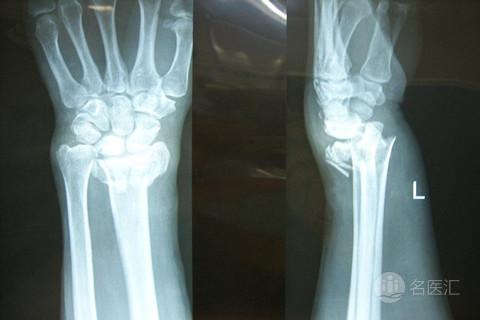

家长必须了解儿童骨折的康复治疗包括两个阶段:骨折复位后石膏固定期是康复治疗的第一阶段,由于在这一时期骨折部位有坚固的内固定或石膏外固定,康复治疗的内容可以有如下安排:冷、热疗、低频神经电刺激疗法、损伤部位应尽早进行肌肉的等长收缩,帮助患儿抬高患肢,鼓励其进行肢体远端未固定关节的的主动运动,促进静脉回流和减轻肿胀,同时,尽早在不引起病情或疼痛加重的情况下进行关节活动和邻近关节的各个轴面的关节活动,先进行轻柔运动,动作缓慢均匀,待肌肉弹性,肌力有所改善后,再逐渐加大运动幅度与运动量,同时定期复查X摄片,及时了解骨折愈合情况和康复治疗的有效性。术后及外固定拆除后的综合康复是治疗的第二阶段,康复治疗内容包括以下几个方面:关节活动度的训练(持续的被动训练、热疗、关节松动术、矫形支具的应用等)和增加肌力的训练(助力运动、主动运动、生物反馈训练等),这两个阶段的治疗是骨折发生后,孩子全面恢复的不可缺少的途径,否则,孩子可能要很长时间才能恢复功能或功能恢复不佳。

实践证明,骨折复位固定后,如果及时进行正确的功能锻炼,给骨折线以垂直的生理性压力,可以促进骨组织的增生,加速骨折愈合,防止肌肉挛缩和粘连、并使已经粘连和挛缩的关节功能逐步恢复,增加肌力,使孩子受伤部位得到最大程度的恢复。因此术后或外固定拆除以后,早期进行专职康复医师的悉心指导、介入正规的、儿童适宜的综合康复方法,是骨关节疾病缩短病期、避免或减轻后遗残疾、功能完全恢复的重要手段,但*力暴**运动和非正规的康复方法是严格禁止的,方法不当,则会引起骨化性肌炎、疲劳骨折等严重后果。